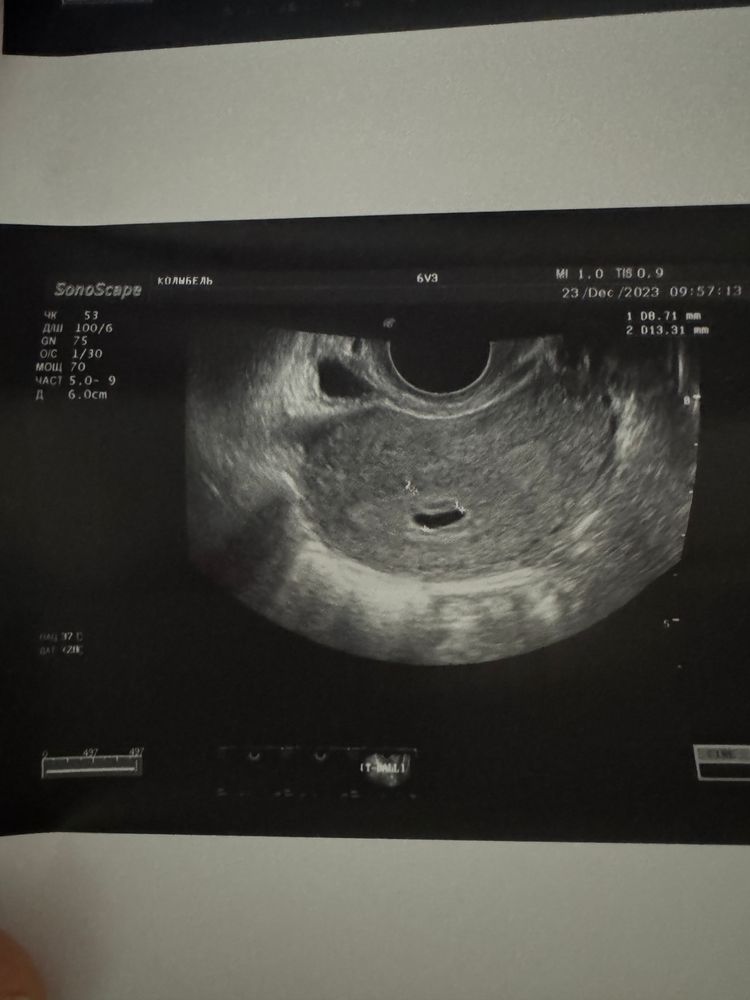

На 19 дпп было только плодное яйцо, а вот сейчас растем и развиваемся, на УЗИ уже ручкой маме машем)))

23.12.2023